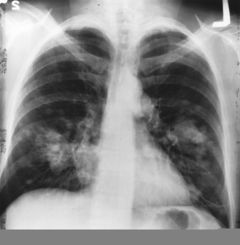

Chest radiograph showing lung cancer.

سرطان الرئه ;الصدر بالاشعه السينيه تبين ورم سرطاني في الرئه اليسرى